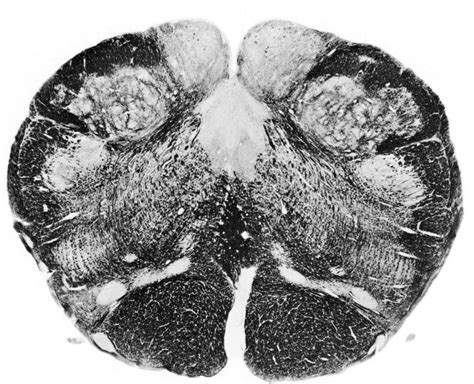

Alright, let’s talk about how we actually see and label this important part of the spine. Medullary cone labeling in medical imaging is a sophisticated process that relies heavily on techniques like Magnetic Resonance Imaging (MRI) and Computed Tomography (CT) scans. These technologies allow us to create detailed cross-sectional images of the spinal cord and surrounding structures. For MRI, it’s particularly useful because it provides excellent contrast between different soft tissues, making the medullary cone and the nerve roots of the cauda equina clearly visible. Radiologists will meticulously examine these images, often in multiple planes (sagittal, coronal, and axial), to pinpoint the exact location of the medullary cone. They look for specific anatomical landmarks, such as the L1-L2 intervertebral disc space, to orient themselves. Labeling the medullary cone involves identifying its superior and inferior borders. The superior border is typically at the level where the spinal cord transitions into the conus medullaris, and the inferior border is where it tapers off into the filum terminale. Sometimes, there might be variations in where the medullary cone ends, especially in children, and accurate labeling helps identify these deviations. CT scans, while offering less soft tissue detail than MRI, can be useful for visualizing bony structures and can sometimes complement MRI findings, especially in cases of trauma where bone fragments might be present. Contrast agents might also be used in both MRI and CT to enhance the visibility of certain tissues or abnormalities, like tumors or inflammation, around the medullary cone. The process of medullary cone labeling isn’t just about drawing a line on a scan; it requires a deep understanding of spinal anatomy and potential pathologies. Radiologists use specialized software to measure dimensions, identify any abnormalities like cysts, tumors, or signs of compression (e.g., a flattened conus), and document their findings precisely. This detailed labeling is what guides the treating physicians in making diagnoses and planning interventions. Think about it: if a surgeon needs to operate near the medullary cone, they absolutely need a radiologist’s report that clearly labels the extent of the problem and the precise location relative to the cone. It’s a team effort, really, where advanced imaging and expert interpretation come together to provide the best care. The consistent and accurate labeling of the medullary cone ensures that medical professionals worldwide are on the same page when discussing a patient’s condition, fostering effective communication and collaboration.

So, how do we make sure we get the medullary cone labeled exactly right? It’s all about using the best tools and techniques available. As we touched upon earlier, Magnetic Resonance Imaging (MRI) is the gold standard. MRI uses powerful magnets and radio waves to create incredibly detailed images of the spinal cord and surrounding soft tissues. When imaging the lumbar spine, radiologists typically obtain images in the sagittal plane (a side view), which clearly shows the entire length of the spinal cord, including its tapering end – the medullary cone. They look for specific anatomical landmarks. The superior aspect of the medullary cone usually lies at the level of the L1 vertebral body or the L1-L2 intervertebral disc space. The inferior tip tapers off, eventually merging with the filum terminale. Labeling the medullary cone involves identifying these superior and inferior boundaries precisely on the sagittal view. Axial images (cross-sections) are also crucial for assessing the spinal canal’s diameter and the relationship of the cone to other structures. Sometimes, Computed Tomography (CT) scans might be used, particularly in trauma settings or when MRI is contraindicated. While CT provides excellent detail of bone, it’s less effective for soft tissues. However, with advanced multi-detector CT scanners, radiologists can reconstruct detailed images of the spinal cord and often identify the medullary cone, especially when looking for bony abnormalities that might be compressing it. The technique for accurately labeling also involves understanding anatomical variations. In children, the medullary cone typically terminates lower, around the L3 vertebral level. Recognizing these age-related differences is part of accurate labeling. Radiologists often use specialized software that allows them to manipulate the images, zoom in on details, and take precise measurements. They will annotate the images, clearly indicating the superior and inferior margins of the conus medullaris. They also look for signs of pathology that might affect the cone’s appearance, such as abnormal signal intensity on MRI, which could indicate inflammation, ischemia, or tumor infiltration. Ensuring accuracy in labeling is a meticulous process that combines technical expertise in operating imaging equipment with deep anatomical knowledge and the ability to interpret subtle findings. This rigorous approach guarantees that the information provided to clinicians is reliable, forming the bedrock for confident diagnosis and effective treatment strategies. It’s a testament to the precision required in modern medicine.